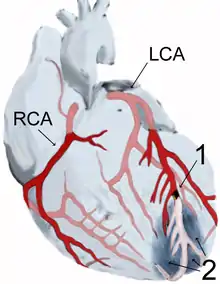

The most common cause of a myocardial infarction is the rupture of an atherosclerotic plaque on an artery supplying heart muscle.[38][70] Plaques can become unstable, rupture, and additionally promote the formation of a blood clot that blocks the artery; this can occur in minutes. Blockage of an artery can lead to tissue death in tissue being supplied by that artery.[71] Atherosclerotic plaques are often present for decades before they result in symptoms.[71]

Cells in the area with the worst blood supply, just below the inner surface of the heart (endocardium), are most susceptible to damage.[75] Ischemia first affects this region, the subendocardial region, and tissue begins to die within 15–30 minutes of loss of blood supply.[76] The dead tissue is surrounded by a zone of potentially reversible ischemia that progresses to become a full-thickness transmural infarct.[74][76] The initial "wave" of infarction can take place over 3–4 hours.[71][74] These changes are seen on gross pathology and cannot be predicted by the presence or absence of Q waves on an ECG.[75] The position, size and extent of an infarct depends on the affected artery, totality of the blockage, duration of the blockage, the presence of collateral blood vessels, oxygen demand, and success of interventional procedures.[29][70]

Abnormalities can help differentiate the location of an infarct, based on the leads that are affected by changes.[17] Early STEMIs may be preceded by peaked T waves.[20] Other ECG abnormalities relating to complications of acute myocardial infarctions may also be evident, such as atrial or ventricular fibrillation.[83]